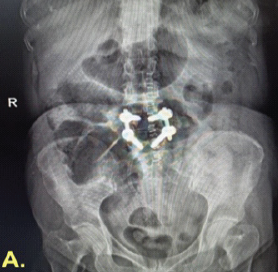

Spinal Aneurysmal Bone Cyst in a Pregnant Patient Presenting with Neurological Symptoms: A Case Report

Bishal Guin , Deepthy Balakrishnan , Arunkumar Sekar , Pavithra Ayyanar